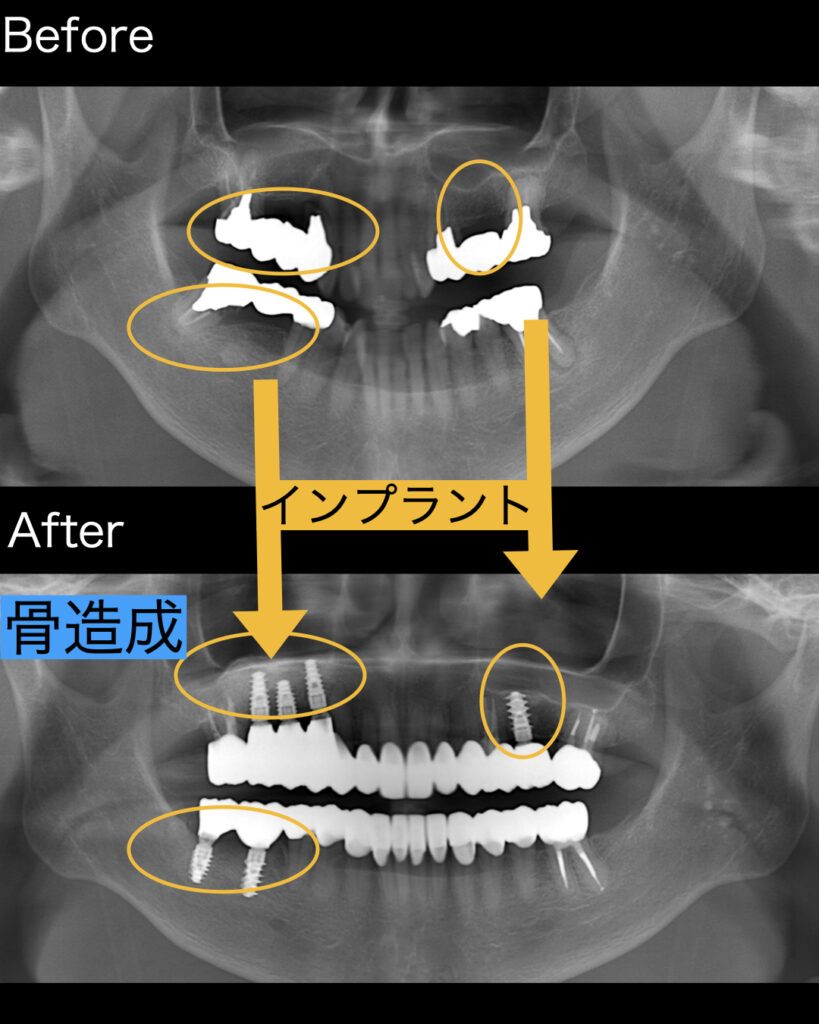

右上に関してはインプラントを保持するだけの骨がなかったため、骨造成を行いました。サイナスリフトという上顎洞に骨補填材を埋入し、6ヶ月ほど経過を待ち、CTによる骨硬化を確認し後にインプラント埋入を行いました。

左上関しても少し骨が少なかったので、ソケットリフトを呼ばれる骨造成を行いました。骨はなければ造ることが可能です。

| 治療内容 | 上4本、下2本のインプラント治療 |